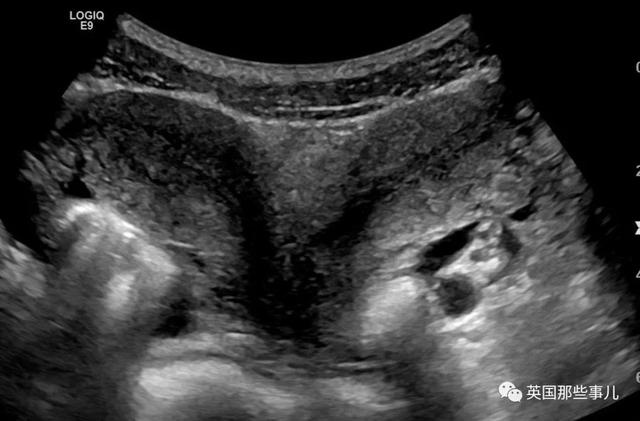

简单点说,就是Melanie的身上有着两个子宫,她的子宫呈爱心形状,带有两个腔室。

(示例图)

两个子宫并不会让怀孕变得困难,但会增加婴儿流产或早产的风险….

到了第12周,Melanie再次来进行例行检测时,医生们又有了新发现,他们告诉Melanie和丈夫,她怀的是三胞胎,而且宝宝们奇迹般地长在不同的子宫里面!

其中一侧是一对双胞胎女宝宝,另一侧是男宝宝。